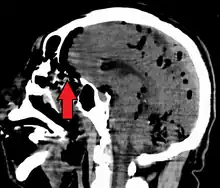

Pneumocephalus and comminuted fracture of the frontal sinus

Pneumocephalus is the presence of air or gas within the cranial cavity. It is usually associated with disruption of the skull: after head and facial trauma, tumors of the skull base, after neurosurgery or otorhinolaryngology, and rarely, spontaneously. Pneumocephalus can occur in scuba diving, but is very rare in this context.